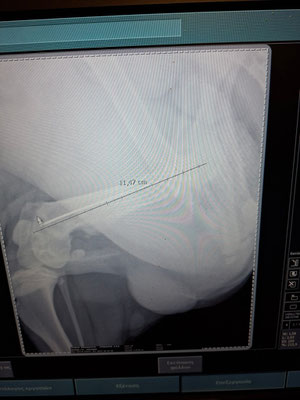

Markos (* 11/2024) hatte keinen leichten Start ins Leben. Er wurde von einem Auto erfasst und schwer verletzt. Die Fahrerin brachte ihn zwar sofort zum Tierarzt, doch danach verschwand sie spurlos – ohne sich um die Kosten zu kümmern oder zu fragen, wie es mit Markos weitergeht. Die Diagnose war erschütternd: Beide Hinterbeine waren gebrochen.

Markos musste operiert werden und verbrachte viele Tage in der Klinik. Trotz seiner schweren Verletzungen war es ein kleines Wunder, dass er nach den Operationen wieder laufen konnte. Der Tierarzt bat uns, Markos bei uns im Tierheim aufzunehmen, um ihm die Chance auf ein liebevolles und glückliches Leben zu geben – und diese Chance möchten wir ihm unbedingt ermöglichen!

Markos wurden die Metallplatten aus den Beinen entfernt. Nun befindet sich nur noch ein langer Nagel in einem der Beine, der mit dem Knochen mitgewachsen ist und dauerhaft dort bleiben wird. Ein Bein ist etwas kürzer als das andere, was zu einem leichten Hinken führt. Es besteht die Möglichkeit, dass er in der Zukunft eine weitere Operation benötigen wird. Aktuell geht es ihm jedoch gut – er läuft, rennt und spielt ganz normal. Mit seinen Artgenossen versteht er sich wunderbar.